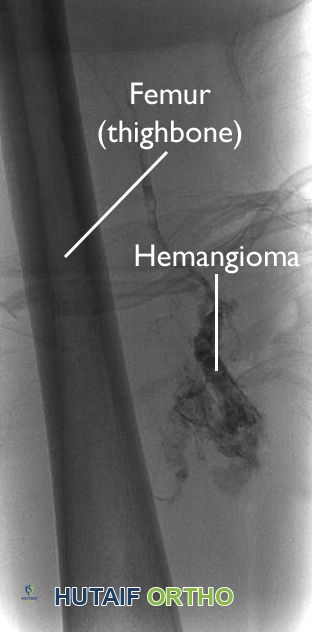

3. تصوير الأوعية الدموية وسدها (Angiography & Embolization)

أورام العمود الفقري، خاصة بعض الأنواع النقيلية (مثل أورام الكلى والغدة الدرقية)، تكون غنية جداً بالأوعية الدموية. لتقليل النزيف الكارثي أثناء الجراحة، يتم إجراء قسطرة للأوعية الدموية المغذية للورم وحقن مواد لسدها (Embolization) قبل الجراحة بيوم أو يومين. هذه الخطوة حيوية جداً وتزيد من أمان الجراحة بشكل كبير.